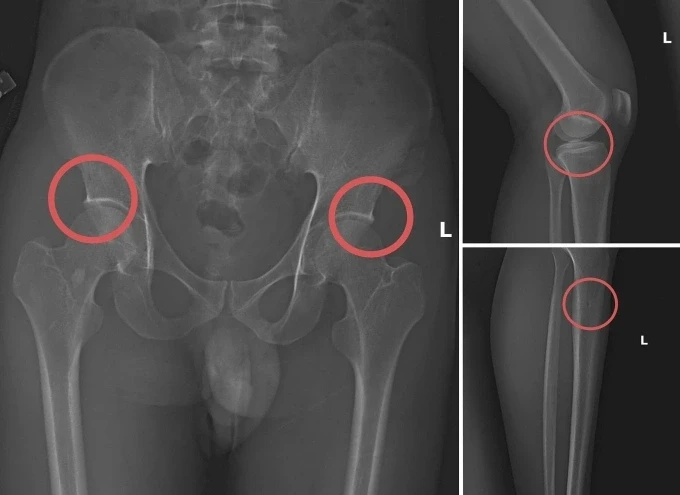

Các vết thương do Châu tự tạo nên. Ảnh: Công an cung cấp

Tại đây, đối tượng Châu tiêm thuốc mê vào tĩnh mạch tay phải của người mua bảo hiểm, sau khoảng 1 phút họ bị mê đi thì Châu sẽ dùng búa và kim tiêm đục, đâm vào vùng cơ thể đã thống nhất từ trước để tạo vết tổn thương trên xương cho nứt, vỡ (thường sẽ làm rạn nứt, vỡ vùng xương chậu, xương đùi…).